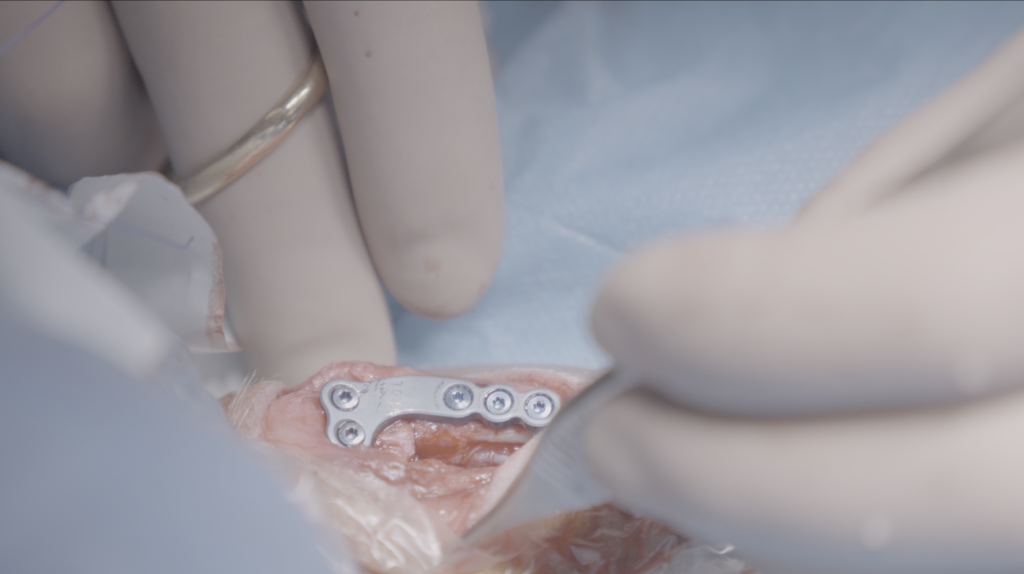

Po zmianie kąta nachylenia powierzchni stawowej kości piszczelowej jest ona stabilizowana przy użyciu specjalnej, anatomicznie dopasowanej płyty ortopedycznej oraz śrub.

Płyty Securos PAX, Arthrex TPLO System, iWET TPLO System są implantami, które na codzień używane są w naszej Klinice